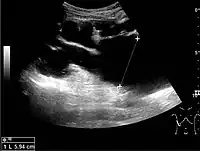

![]() Doppler ultrasound (US) of a normal adult kidney with the estimation of the systolic velocity (Vs), the diastolic velocity (Vd), acceleration time (AoAT), systolic acceleration (Ao Accel) and resistive index (RI). Red and blue colors in the color box represent flow towards and away from the transducer, respectively. The specrogram below the B-mode image shows flow velocity (m/s) against time (s) obtained within the range gate. The small flash icons on the spectrogram represent initiation of the flow measurement.[1] | |

Doppler ultrasonography of the kidney is widely used, and the vessels are easily depicted by the color Doppler technique in order to evaluate perfusion. Applying spectral Doppler to the renal artery and selected interlobular arteries, peak systolic velocities, resistive index, and acceleration curves can be estimated (Figure 4) (e.g., peak systolic velocity of the renal artery above 180 cm/s is a predictor of renal artery stenosis of more than 60%, and a resistive index, which is a calculated from peak systolic and end systolic velocity, above 0.70 is indicative of abnormal renovascular resistance).[1]